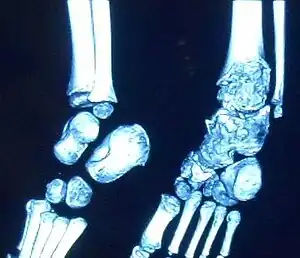

3D CT image of Trevor's disease of the ankle and talus.

This disorder is rare, and is characterised by an asymmetrical limb deformity due to localized overgrowth of cartilage, histologically resembling osteochondroma. It is believed to affect the limb bud in early fetal life. The condition occurs mostly in the ankle or knee region and it is always confined to a single limb. This usually involves only the lower extremities and on medial side of the epiphysis. It is named after researcher David Trevor.[1]

Trevor disease was first described by the French surgeon Albert Mouchet and J. Belot in 1926. In 1956, the name "dysplasia epiphysealis hemimelica" was proposed by Fairbank.[1] The usual symptoms are the appearance of an osseous protuberance, on one side of the knee, ankle or foot joint which gradually increases Radiologically,[14] the condition shows a nonuniformity of growth and multiple unconnected ossification centers around the epiphyses.[8]